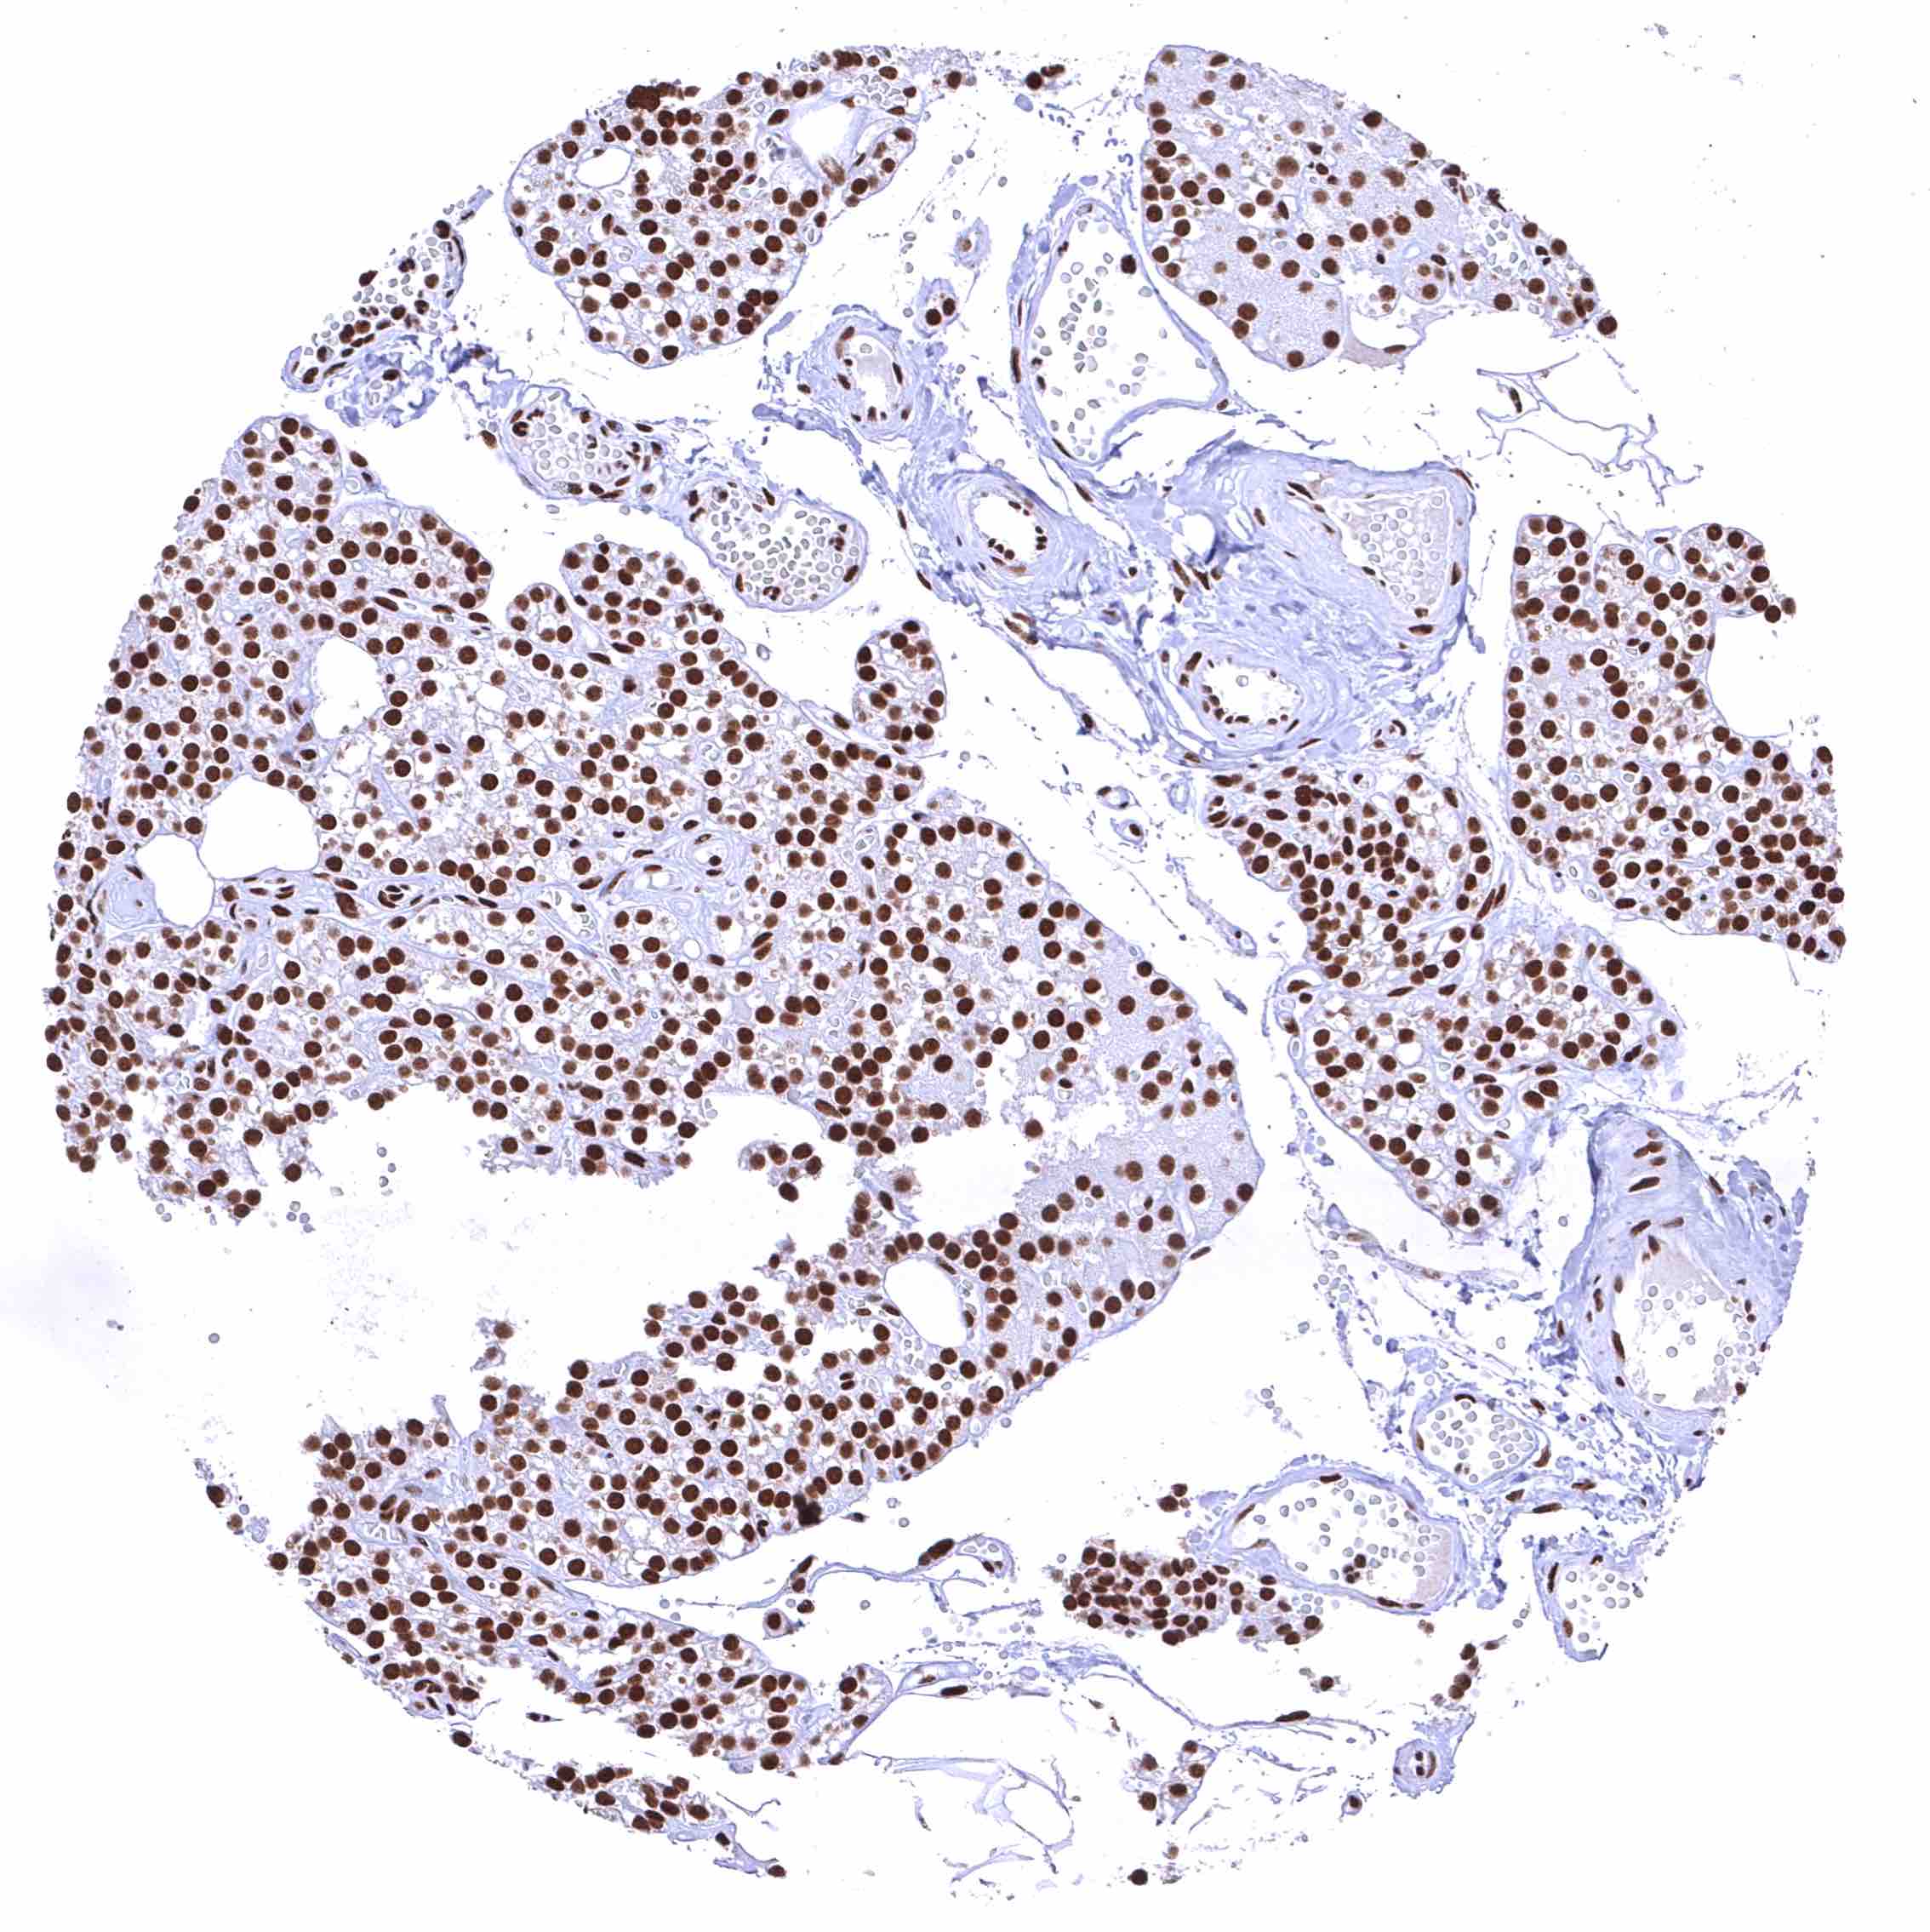

Prostate – BRD4 staining of basal cells is somewhat stronger than of acinar cells.